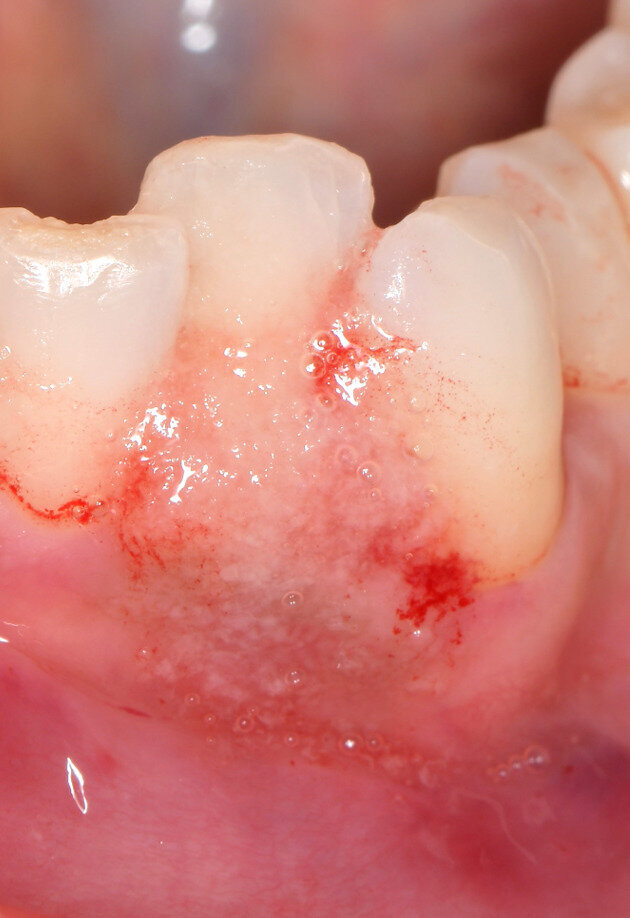

Fig. 6 - Visione occlusale del difetto trattato a 7 giorni di follow-up. Notare l’assenza di infiammazione e il tessuto guarito.